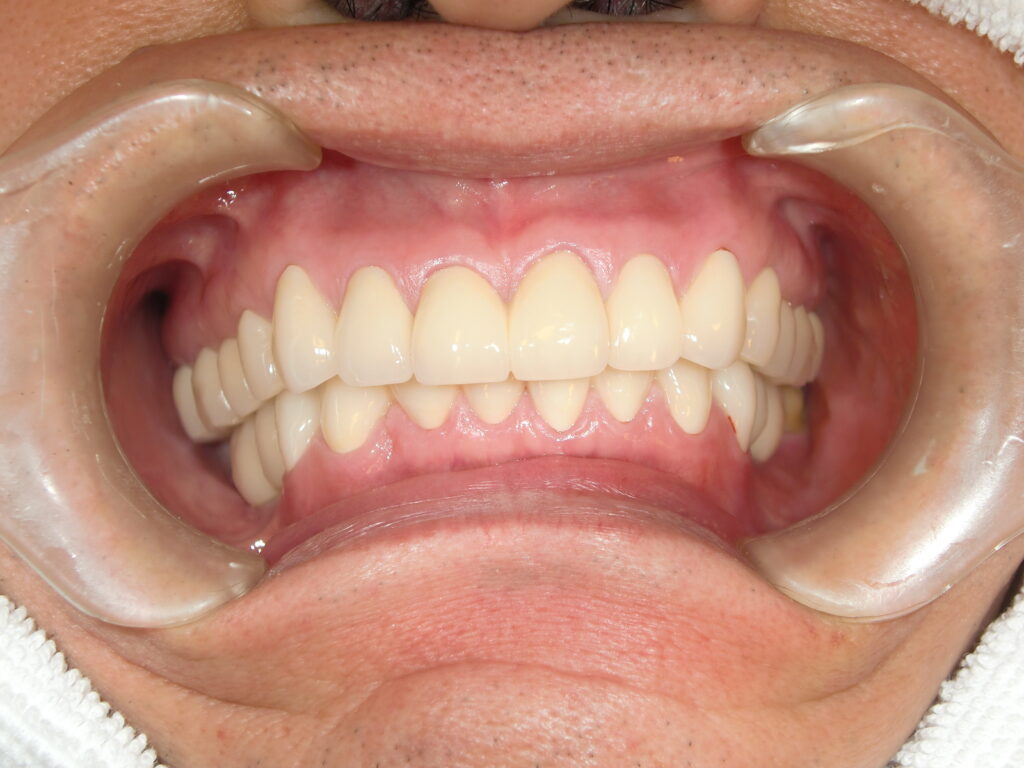

患者様の状態・ご希望 「右上の奥歯が取れちゃった」「ほとんど根っこが残っていないみたいなの。」 20年以上メンテナンスにかよってくださっている患者様です。 「私の上あごって上顎洞があって骨が薄いんでしょ」 「左上の奥歯の時はお世話になりました、苦労してオペしていただきまし…